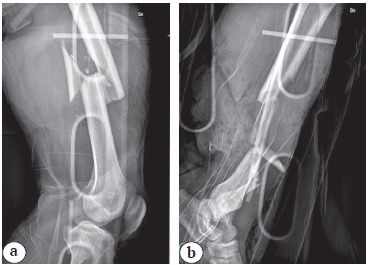

In October 2018, he was evaluated at our hospital for clinical signs of infection with the presence of sinus and drainage in the distal third of the left leg. After clinical evaluation it was requested FDG PET-CT (fluoro-D-glucose positron emission computed tomography), which highlighted and confirmed the focus of osteomyelitis in correspondence with the previous docking site (Figure 3). To complete the diagnosis, x-ray and CT scan of the leg was performed (Figure 4).

Figure 3. Clinical signs of infection with sinus and drainage (a); FDG PET-CT shows and confirms infection with uptake at the level of previous docking site (b)

Figure 4. Lateral X-ray (a) and CT scan (b) before second Ilizarov fixator: a — purple and blue lines show the Caton-Deschamps ratio (lower limit of 0.60). A white oval shows area of tibial tubercle; b — purple lines delimit atypical extension of the patellar tendon